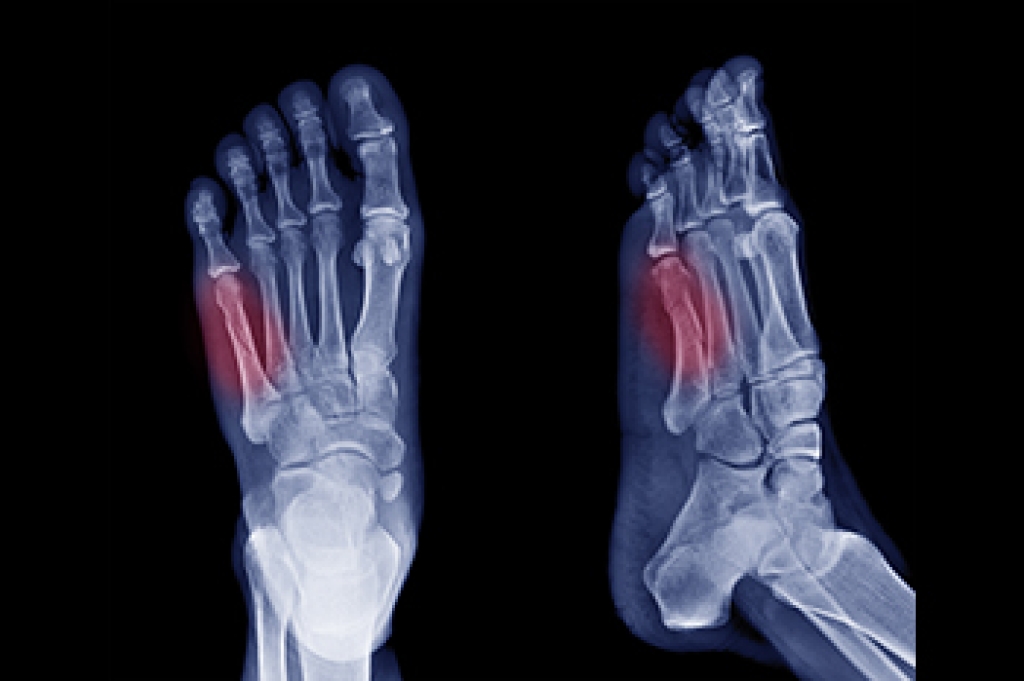

A dancer's fracture is a break in the shaft of the 5th metatarsal, the long bone on the outer side of the foot. This injury is typically caused by twisting motions, awkward landings, or direct trauma. It is common among dancers and athletes but can happen to anyone. Symptoms of a 5th metatarsal fracture include sharp pain on the outer side of the foot, swelling, bruising, tenderness, and difficulty walking. Diagnosis is made through a physical examination and imaging, such as X-rays, to determine the exact location and severity of the fracture. Treatment often involves immobilizing the foot with a cast or walking boot to allow the bone to heal properly. In severe cases, surgery may be required to realign and stabilize the bone. A podiatrist can provide expert care and ongoing monitoring to ensure the foot heals correctly and regains full functionality. If you have fractured your foot, it is suggested that you schedule an appointment with a podiatrist for a diagnosis and treatment options.

A broken foot requires immediate medical attention and treatment. If you need your feet checked, contact Dr. Howard Horowitz from Bowie Foot & Ankle . Our doctor can provide the care you need to keep you pain-free and on your feet.

Broken Foot Causes, Symptoms, and Treatment

A broken foot is caused by one of the bones in the foot typically breaking when bended, crushed, or stretched beyond its natural capabilities. Usually the location of the fracture indicates how the break occurred, whether it was through an object, fall, or any other type of injury.

Those that suspect they have a broken foot shoot seek urgent medical attention where a medical professional could diagnose the severity.

Treatment for broken bones varies depending on the cause, severity and location. Some will require the use of splints, casts or crutches while others could even involve surgery to repair the broken bones. Personal care includes the use of ice and keeping the foot stabilized and elevated.

Diagnosing a foot stress fracture requires a thorough evaluation by a podiatrist to identify the source of pain. Patients are typically asked about their medical history, including any past fractures, current medications, and daily activities that may contribute to repetitive stress on the feet, toes, or ankles. A podiatrist will perform a physical examination, applying gentle pressure to the affected area to check for tenderness or localized pain. If a foot stress fracture is suspected, diagnostic imaging is often necessary. X-rays may be taken first, but foot stress fractures can sometimes be challenging to detect immediately after injury and may only become visible once healing begins. In such cases, advanced imaging like MRI scans, ultrasound, or bone scans may be used to confirm the diagnosis and assess surrounding soft tissues. These methods allow a podiatrist to pinpoint the site of the fracture. If you believe you have developed a foot stress fracture, it is suggested that you schedule an appointment with a podiatrist for a diagnosis and treatment options.

Stress fractures occur in the foot and ankle when muscles in these areas weaken from too much or too little use. The feet and ankles then lose support when walking or running from the impact of the ground. Since there is no protection, the bones receive the full impact of each step. Stress on the feet can cause cracks to form in the bones, thus creating stress fractures.